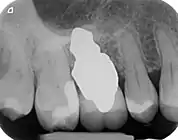

X-ray of root analogue three rooted dental implant right first upper molar.jpg